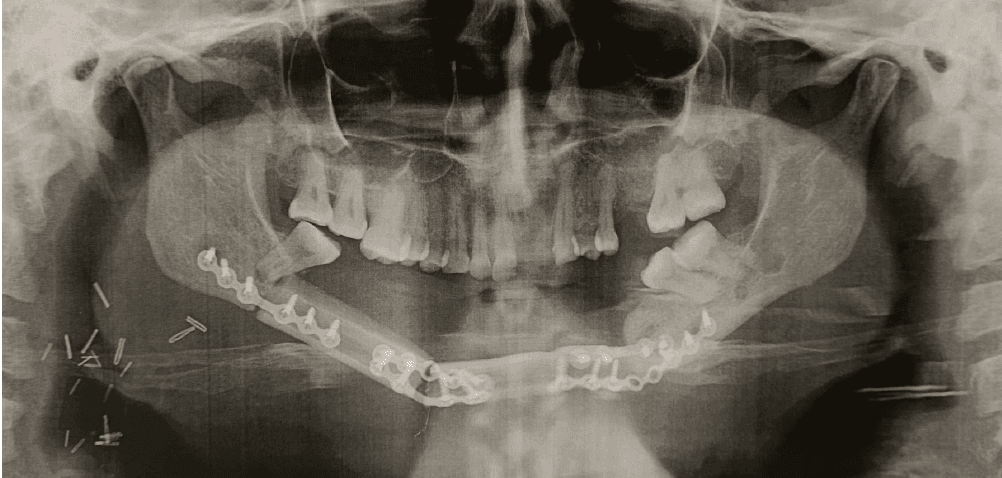

Pour cette première (à la fois en Guinée et à la fois par Enfants Du Noma), le cas a été bien choisi, sans comorbidité associée, et de façon à ne pas être confronté à des soucis de dénutrition ou d’anémie. Il s’agissait d’une patiente guinéenne de 42 ans, qui avait déjà bénéficié à Conakry il y a un an de l’exérèse d’un très volumineux améloblastome (tumeur bénigne) de la mandibule par le Pr Rahiou Diallo. La perte de substance osseuse avait été maintenue par une plaque métallique, mais sans apport osseux. Cette plaque avait fini par s’exposer dans la bouche de la patiente, et il fallait donc recourir à une reconstruction osseuse.

L’intervention a consisté en le prélèvement du péroné droit (fibula) de la patiente, avec de la peau de la jambe pour reconstruire la peau du menton, et surtout avec son artère et ses veines qui ont été « rebranchés » (micro-anastomoses) sous microscope à des vaisseaux au niveau du cou, pour que tous ces tissus soient revascularisés. Il a fallu 2 morceaux de péroné pour reconstruire la forme de la mâchoire, un pour le menton, et l’autre pour la branche horizontale droite.

Dans les suites de ce type de reconstruction, la surveillance doit être stricte, avec des objectifs stricts concernant notamment la tension artérielle et le taux d’hémoglobine, de façon à ce que les micro-vaisseaux rebranchés ne se « bouchent » pas par un thrombus, ce qui aurait nécessité une ré-intervention en urgence.

Rien de tout cela n’est heureusement survenu. Les suites ont été extrêmement simples et la patiente a été tellement rassurante sur l’ensemble des critères de surveillance, que nous avons autorisé sa sortie dès le 7ieme jour post-opératoire.